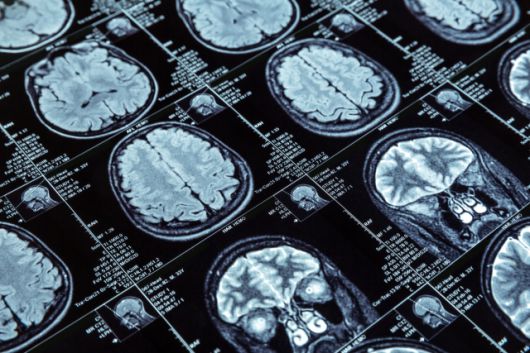

종전에는 알츠하이머병을 진단하려면 뇌척수액을 뽑아내는 요추 천자나 자기공명영상(MRI), 컴퓨터단층촬영(CT) 등 뇌 영상 검사를 주로 이용했다. 반면 루미펄스는 간단한 채혈만으로 이뤄지기 때문에 진단을 수월하게 할 수 있다는 점에서 큰 변화가 예상된다.